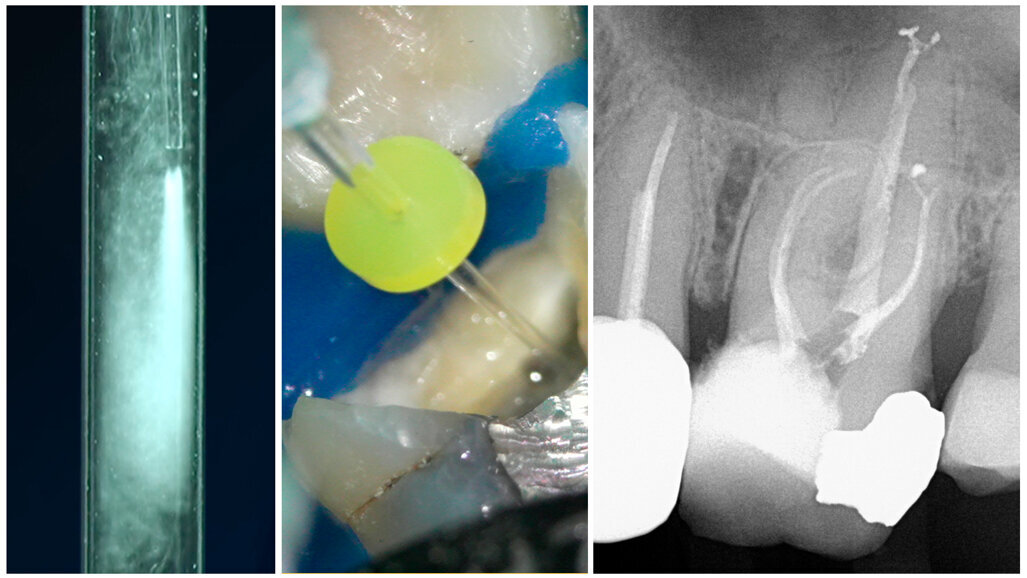

Dr Benedict Bachstein, who practises at Exclusively Endodontics in New Jersey in the US, shared his clinical experience with OdneClean. He and his endodontic team have performed hundreds of OdneClean cases already. The cases he presented and discussed during the summit focused on OdneClean’s ability to help find and clear lateral and other accessory canals, even in vital cases. Also, OdneClean has been highly effective for opening and cleaning joined root canal systems.

Dr Jenny He, who practices at Associates in PIE and is adjunct associate professor at Texas A&M University College of Dentistry in Dallas in the US, spoke about the potent everyday functionality of OdneClean. She contributed documentation on over 50 clinical cases to the Odne clinical study portal and demonstrated the ability of OdneClean to perform fast and thorough cleaning in retreatment situations. She found removal of remnants of sealer and gutta-percha to be demonstrably easier and praised OdneClean’s ability to clean long, narrow, curved canals efficiently.

Dr Jerome Stroumza, who practises at Spruce Dental in San Francisco in the US and owns the EndoImplantology Institute, spoke about his use of OdneClean and OdneFill in his practice. He stated that OdneClean appears to be very helpful in identifying and cleaning mesial canals and that OdneFill offers a reliable high-quality filling. OdneClean and OdneFill represent a paradigm shift in endodontics, since when used in combination, the dentist no longer needs to shape the canal to fit a cone. Root Preservation Therapy enables the cleaning and filling of complex morphologies, preserving as much tooth structure as possible.